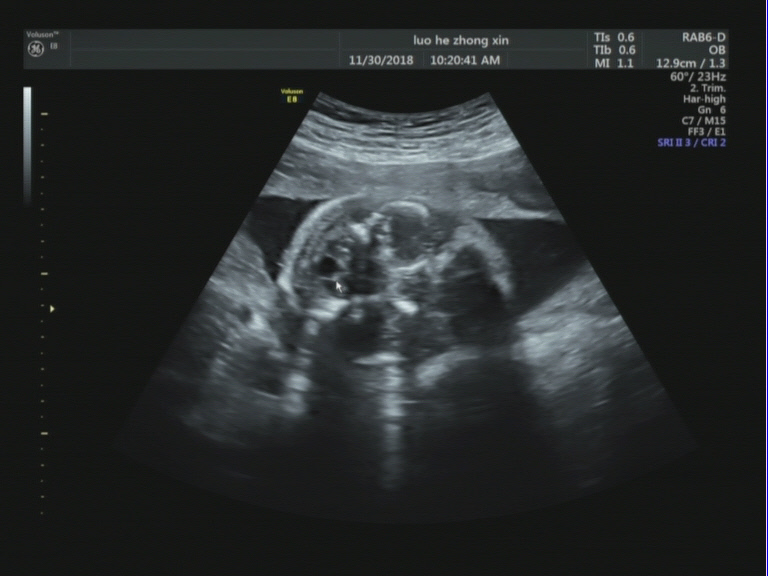

胎儿小脑后方可见一7mmx4mm的无回声。

【超声图像】